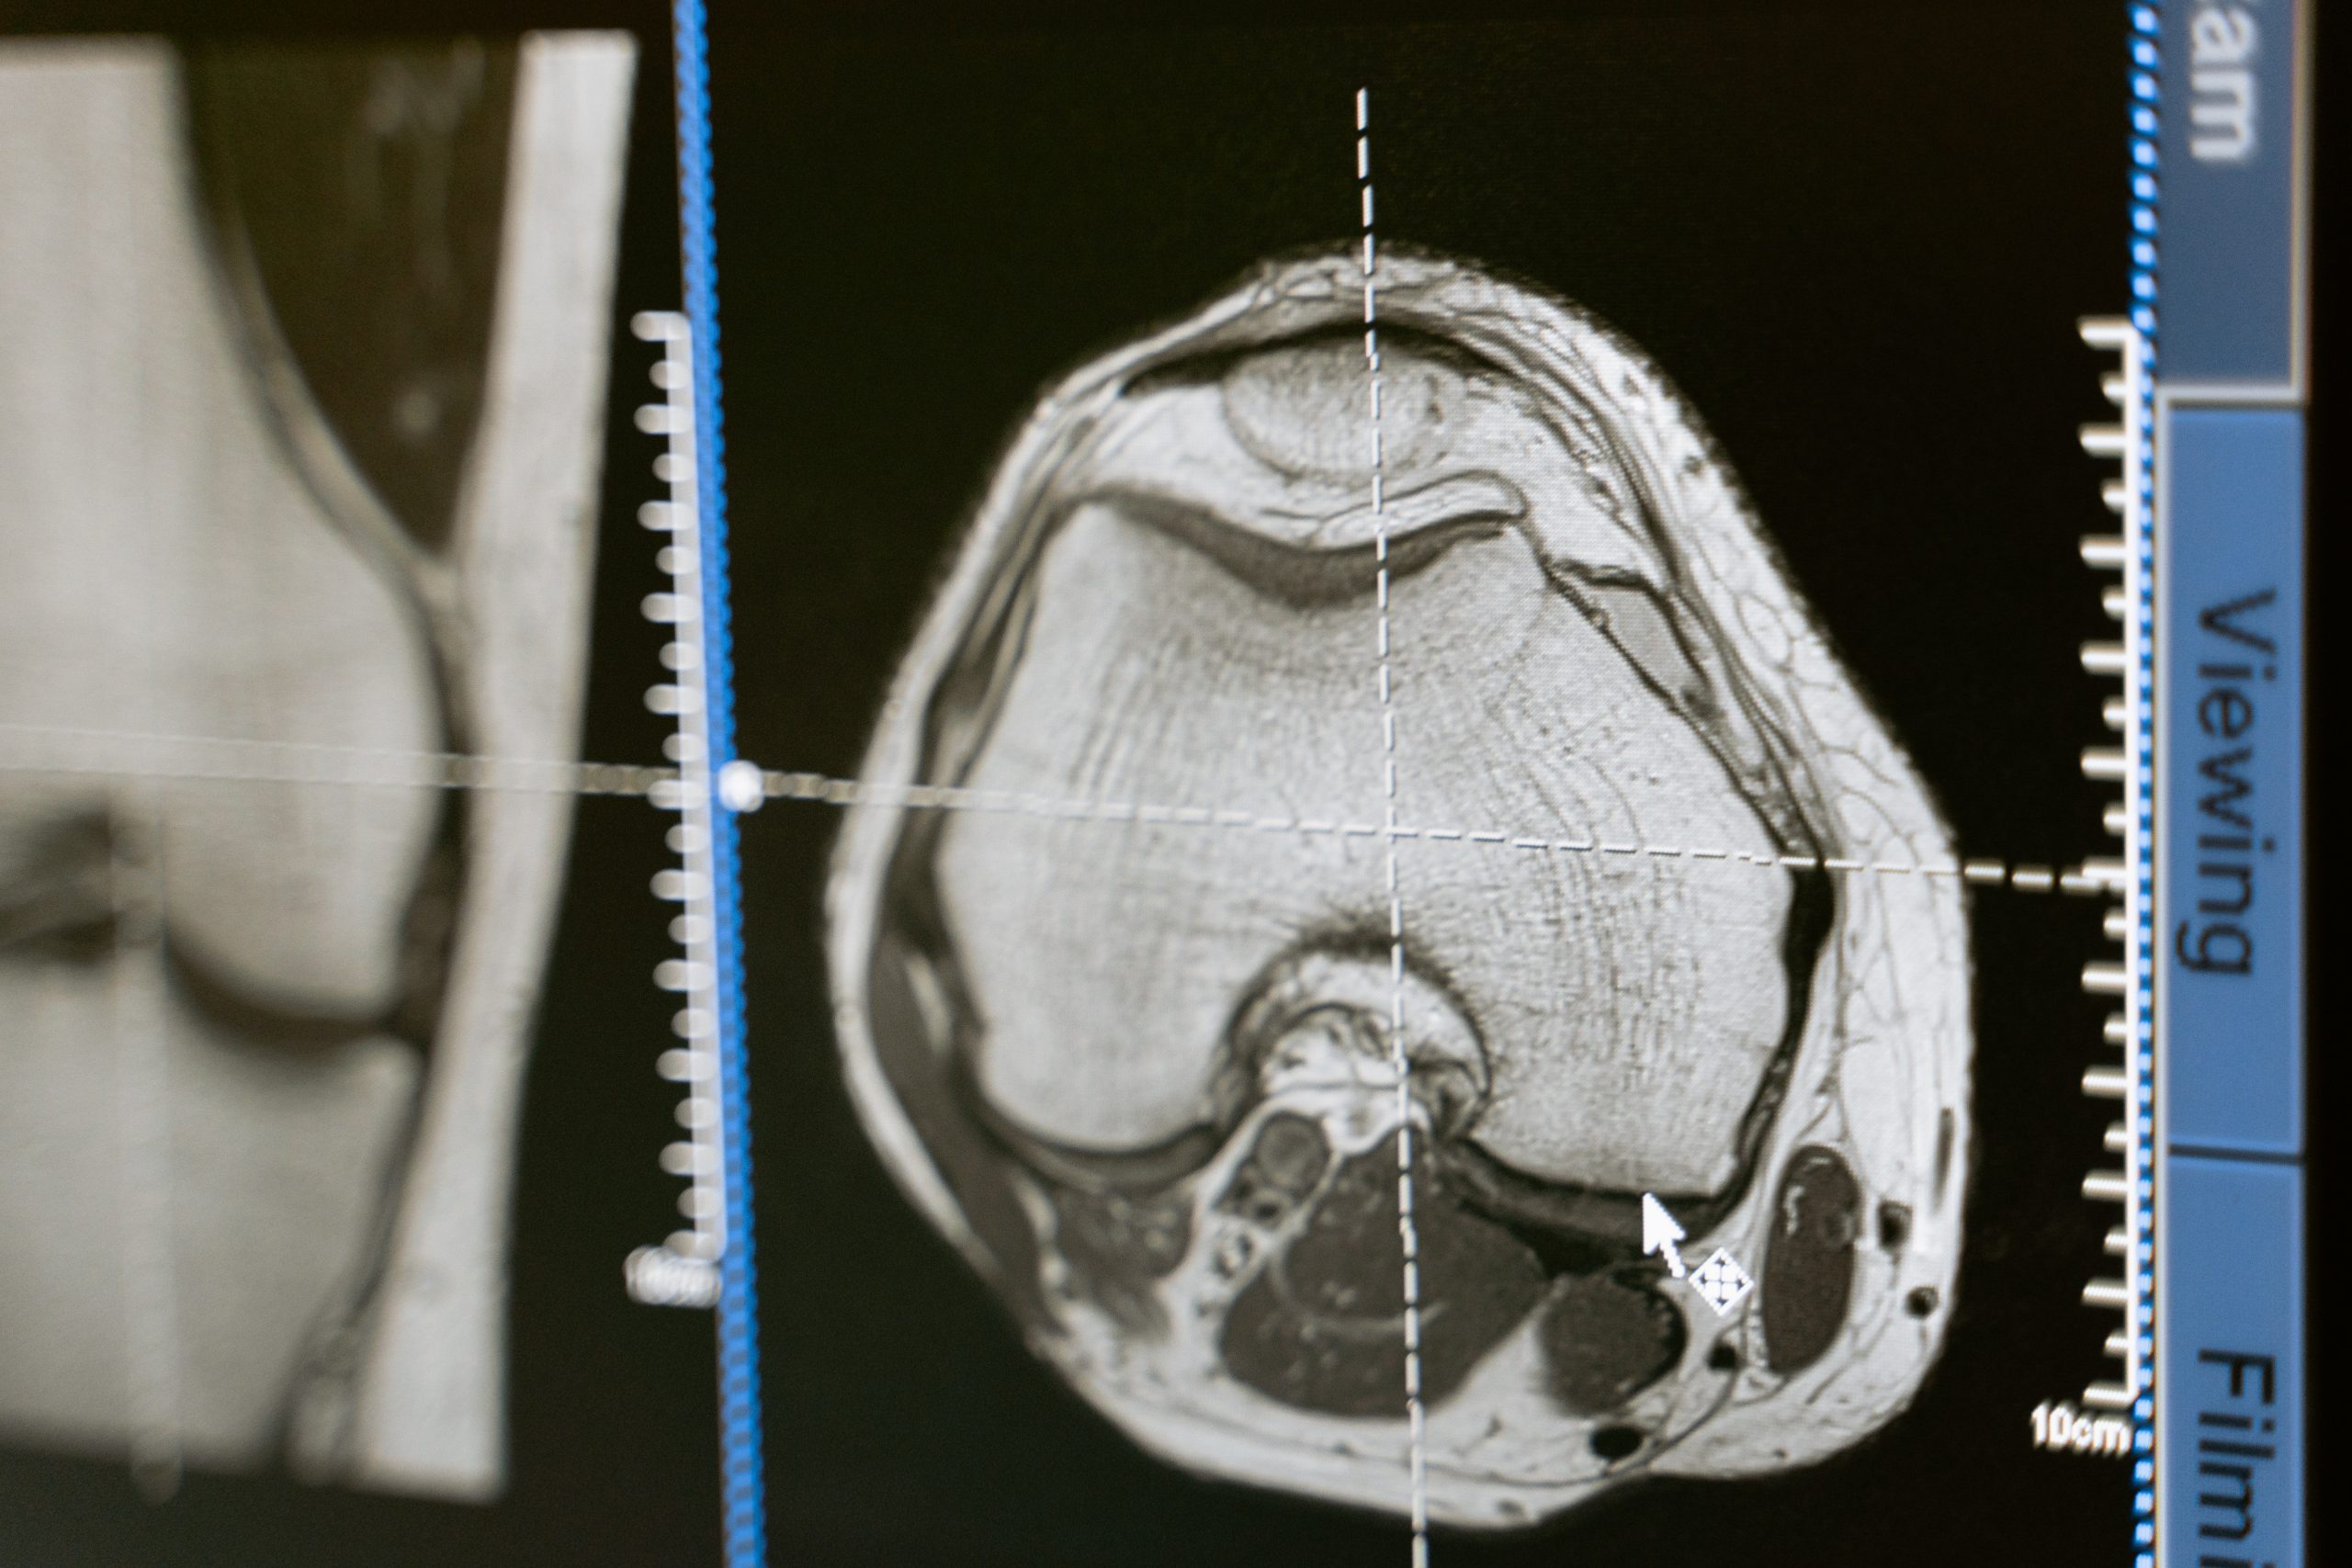

Pesquisadores da Fiocruz, da UFRJ, no Rio, e da Escola de Medicina Albert Einstein e da Universidade de Nova York, nos EUA, decidiram acompanhar o caso recente. Queriam traçar paralelos. O trabalho é fruto da tese de doutorado de Pedro de Freitas, sob orientação do professor Renato Rozental, pesquisador da UFRJ e da Fiocruz. A pesquisa contou com recursos não disponíveis na época do acidente do americano: exames como tomografia, eletroencefalograma, ressonância magnética, modulação da atividade elétrica cerebral e exames neuropsicológicos para avaliar as disfunções no lobo frontal e estimar as consequências da lesão.